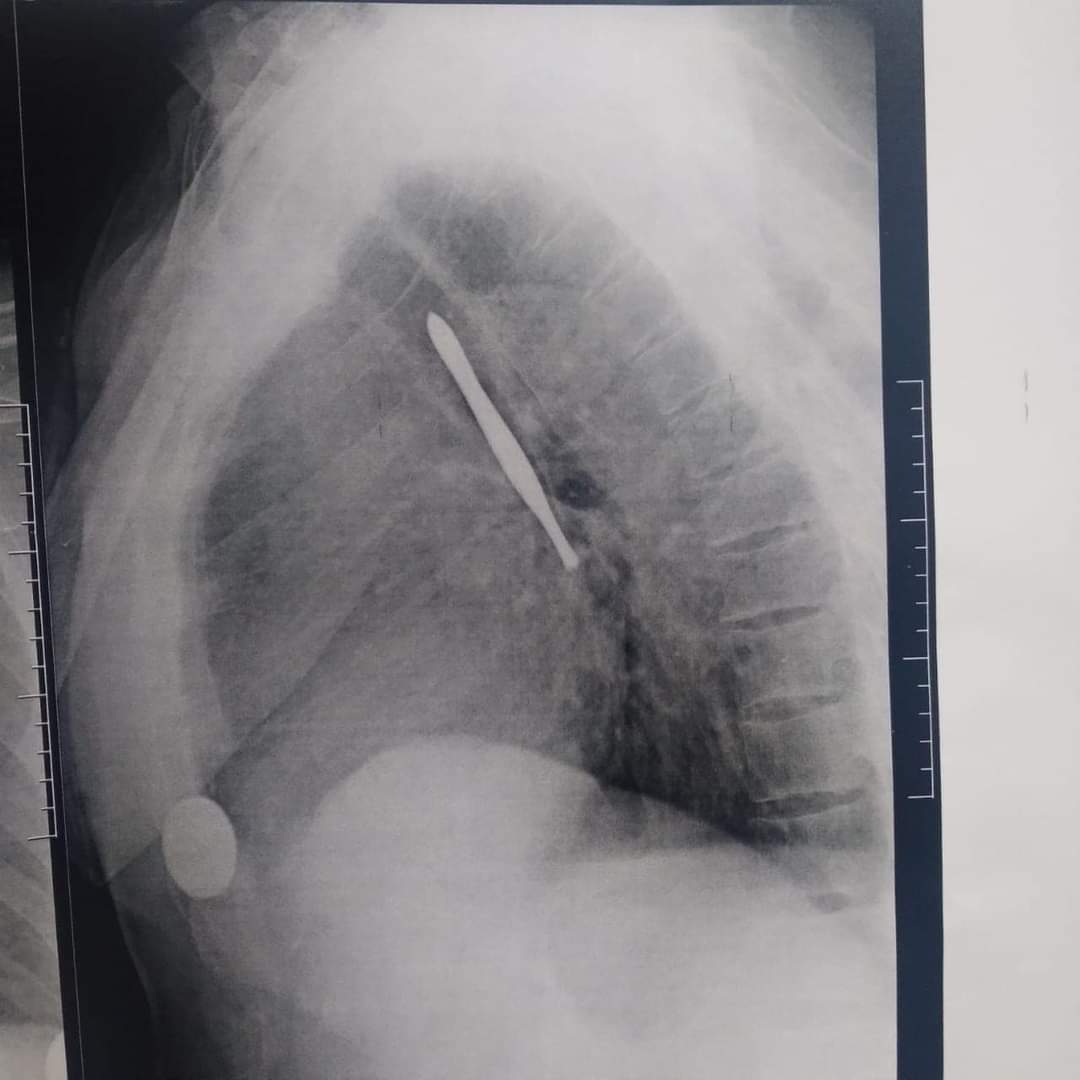

نجح فريق جراحي بقسم جراحة القلب والصدر بمستشفى بنها الجامعى بمحافظة القليوبية، في استخراج ملقاط شعر، من القصبة الهوائية لمريض يعاني من شق حنجري قديم، وأثناء قيامه بتنظيف فتحة الشق الحنجرى بطريقة غير طبية وغير صحيحة باستخدام ملقاط ملفوف بمناديل ورقية، سقط منه وابتلعه ودخل لفتحة القصبة الهوائية.

وأوضح مستشفى بنها الجامعي بمحافظة القليوبية، في بيان له، أنه تم استخراج ملقاط شعر من القصبة الهوائية لمريض يعاني من شق حنجري قديم، وبينما يقوم بتنظيف فتحة الشق الحنجري بطريقة غير طبية وغير صحيحة باستخدام ملقاط ملفوف بمناديل ورقية سقط داخل فتحة القصبة الهوائية.

وتابع المستشفى، أن المريض حضر للقسم في حالة اختناق، وتم دخوله للعمليات فورا، حيث نجح الدكتور باسم مفرح الأستاذ المساعد بالقسم، وبمعاونة الدكتور أحمد الخضري مدرس مساعد التخدير، من استخراج الملقاط، وخرج المريض من العمليات، ويخضع لاستكمال علاجه بالقسم لحين تماثله الكامل للشفاء.